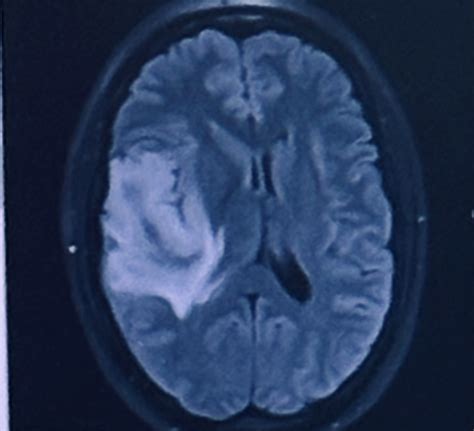

The Kip Kinkel brain scan was conducted as part of a broader effort to understand the neurological basis of violent behavior. The scan revealed several abnormalities in Kinkel's brain, particularly in areas associated with impulse control, emotion regulation, and decision-making. These findings have been pivotal in advancing the field of forensic neuroscience, offering a glimpse into how neurological factors might contribute to violent acts.

One of the key findings from the Kip Kinkel brain scan was the presence of reduced activity in the prefrontal cortex, a region of the brain crucial for executive functions such as impulse control and decision-making. This area is often referred to as the brain's "control center," and its dysfunction can lead to impulsive and aggressive behavior. Additionally, the scan showed abnormalities in the amygdala, a region involved in processing emotions, particularly fear and aggression.

These neurological abnormalities suggest that Kinkel may have had difficulty regulating his emotions and controlling his impulses, factors that could have contributed to his violent actions. However, it is important to note that neurological findings alone do not explain complex behaviors like school shootings. Environmental, psychological, and social factors also play significant roles.